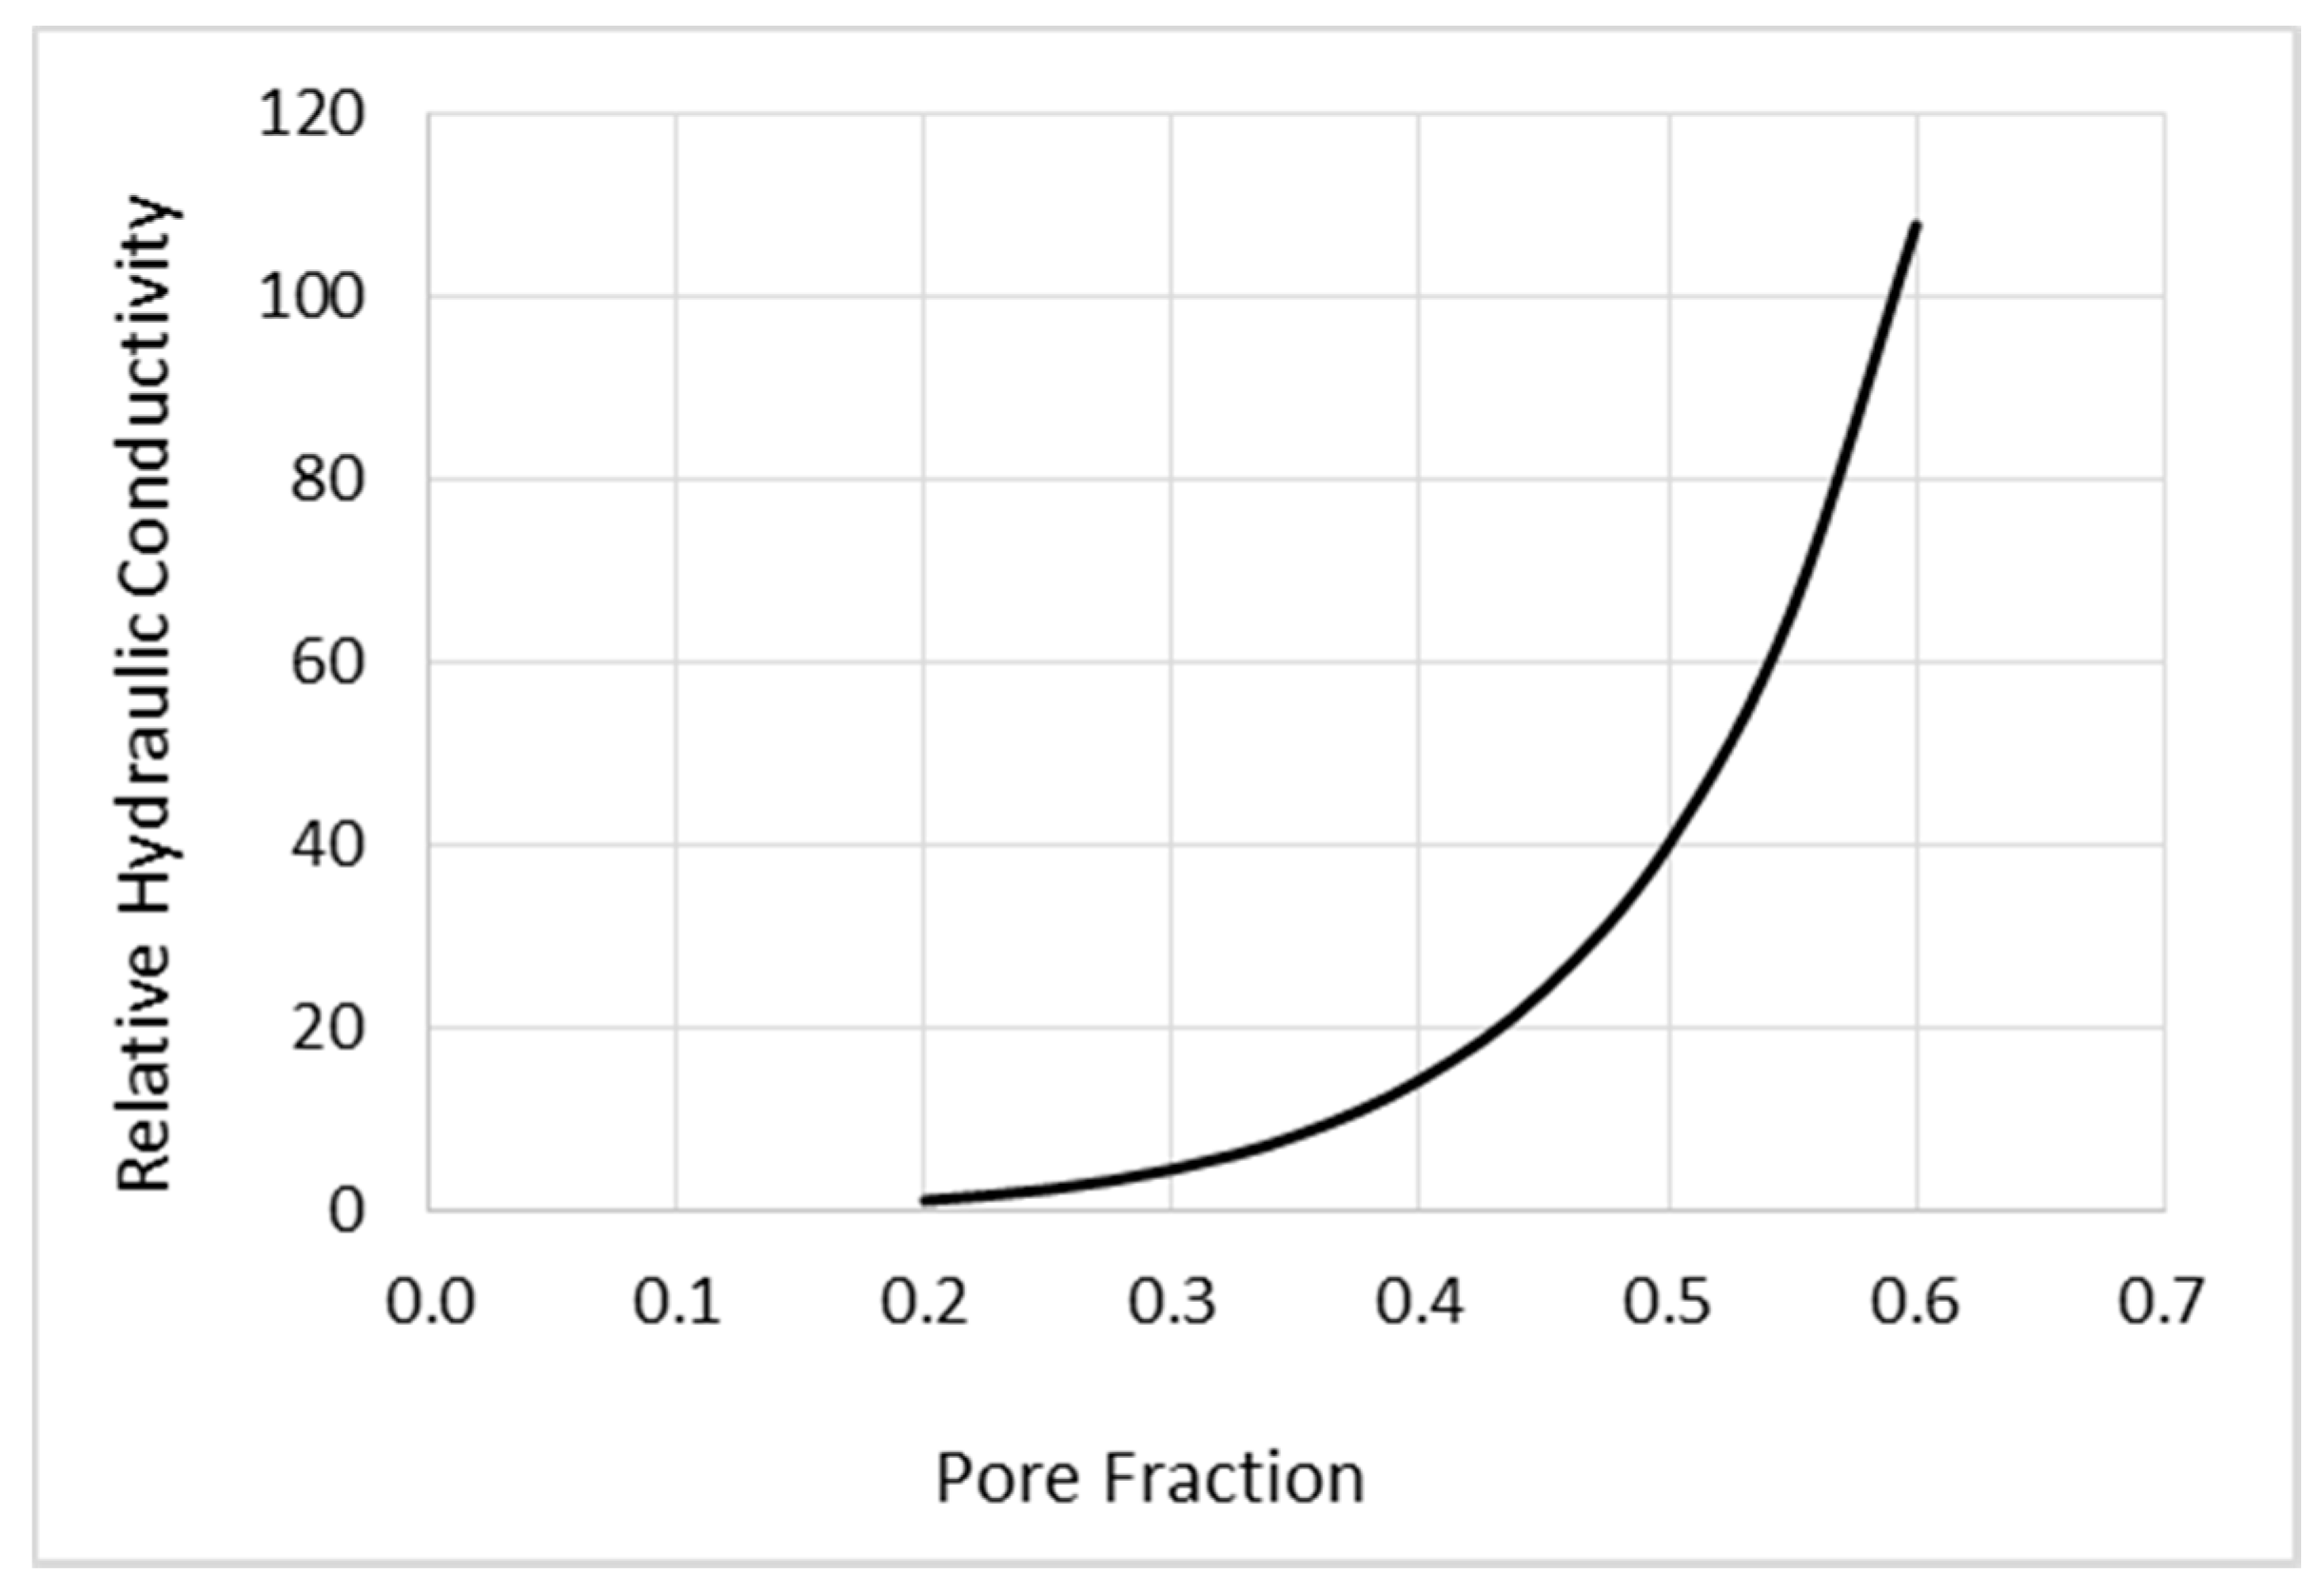

2.1. Simulation Models and Methods

2.1.1. Mathematical Modeling of CED

2.1.2. Simulation Methods